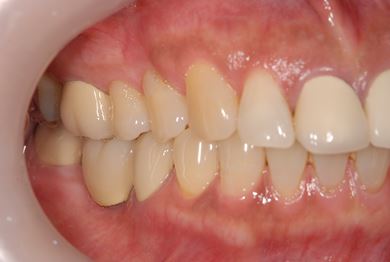

骨再生インプラント治療+セラミック治療+歯肉歯槽骨整形手術

| 性別/年齢 | 女性 / 57歳 | ||||||||||||||||||||||||||||||||

| 主訴 | 左奥上の歯ぐきの痛みの治療相談。 | ||||||||||||||||||||||||||||||||

| 治療内容 | インプラント2本(ソケットリフト、GBR)、メタルボンドセラミッククラウン3本、歯肉歯槽骨整形手術 | ||||||||||||||||||||||||||||||||